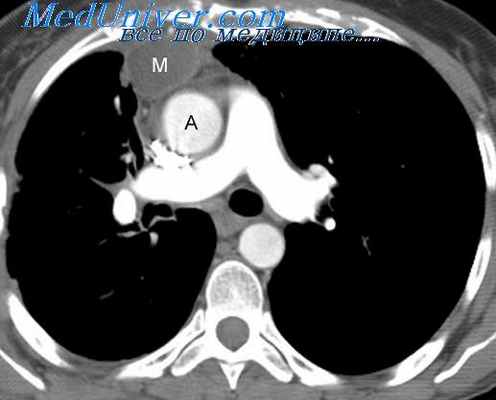

Обязательный перечень рентгенологических исследований включает рентгенографию грудной клетки, рентгенографию пищевода с контрастированием, компьютерную томографию. В большинстве случаев проведенное обследование позволяет установить локализацию рака средостения и распространенность процесса, заинтересованность органов грудной полости (легких, диафрагмы, аорты, грудной стенки). Уточнить состояние мягких тканей в зоне новообразования, выявить метастазы опухоли в лимфоузлы и легкие помогает МРТ.

Для того, чтобы поставить диагноз, пациента направляют на рентгенографию грудной клетки, пищевода с контрастированием и компьютерную томографию. Обследование позволяет установить точную локацию рака средостения, обширность процесса, поражение других органов грудной полости — легких, диафрагмы, аорты, грудной стенки. Узнать состояние мягких тканей в зоне новообразования, а также выявить метастазы опухоли в лимфоузлы и легкие дает возможность МРТ.